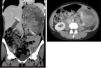

A propósito de un caso: tumor mixto epitelial y estromal del riñón con evolución sarcomatosa

Figuras (3)